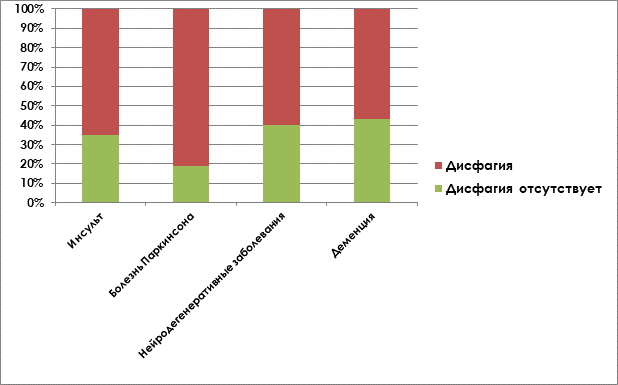

Дисфагия по происхождению может быть ротоглоточной или пищеводной. Установлено, что встречаемость дисфагии зависит от возраста пациентов и нозологии, при которых развивается данный симптом [5]. Дисфагия диагностируется чаще при травмах головы, шеи, при онкологических заболеваниях полости рта и горла у молодых пациентов, при поражении ЦНС у людей старшего возраста [1] (рис.1).

Рис.1. Распространенность дисфагии при различных неврологических заболеваниях.

Примечание: составлен авторами по результатам источников [1–5]